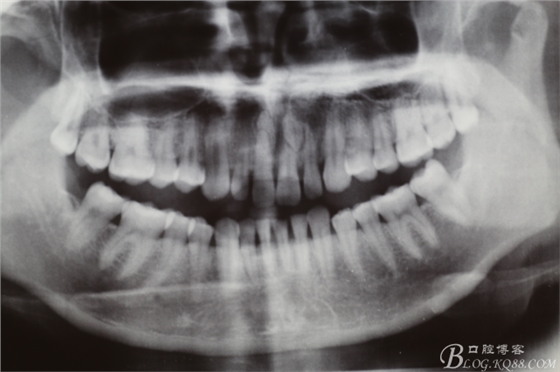

圖3.術(shù)前全景片檢查:11和21的根尖區(qū)各有一枚倒置多生牙